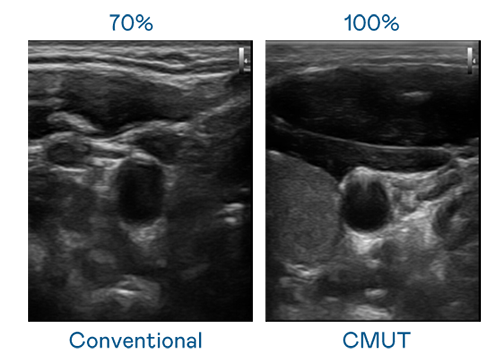

CMUT 技术是一种用电容式微机电元件来产生超音波讯号的技术。与传统 PZT 压电式技术相比,CMUT 频宽增加 30%,更宽频的超音波讯号让影像解析度大幅提升,是实现高影像品质医疗超音波扫描、促进精准医疗发展的关键技术。

超音波影像的解析度高低,首先取决于探头能发出的讯号频宽。z6com·尊龙 CMUT 可提供高清晰的超音波讯号,提供高频宽、高灵敏度、影像纹理细节更高的超音波影像,协助医护人员缩短影像判读时间及利用精准的医疗影像进行诊断。